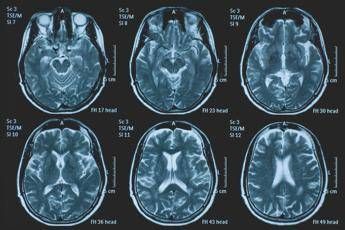

(Adnkronos) – La Commissione europea (Ce) ha autorizzato la commercializzazione condizionata di tovorafenib come monoterapia per il trattamento dei pazienti di età pari o superiore a 6 mesi con glioma pediatrico di basso grado che presentano una fusione o un riarrangiamento del gene Braf o una mutazione Braf-V600, in progressione di malattia dopo una o più terapie sistemiche precedenti. Lo annuncia Ipsen, in una nota, precisando che si tratta della “prima terapia mirata” per questa patologia e che la decisione della Ce si riferisce ai 27 Stati membri della Ue, oltre a Islanda, Liechtenstein e Norvegia. Ogni anno in Ue vengono diagnosticati più di 800 nuovi casi di glioma pediatrico di basso grado (pLgg) con alterazione di Braf. Questo tumore cerebrale, nonostante sia classificato di basso grado (a lenta progressione), comporta un carico significativo e permanente che accompagna la persona per tutta la vita, causando spesso importanti compromissioni fisiche e neurologiche, tra cui perdita della vista, difficoltà di linguaggio e disfunzioni motorie, che possono incidere in modo significativo sull’istruzione, l’autonomia e la qualità di vita a lungo termine del bambino. Finora, molti bambini con pLgg hanno dovuto sottoporsi a interventi chirurgici invasivi, a più cicli di chemioterapia e a radioterapia, con conseguenti complicazioni della salute.   “Per i piccoli che ricevono la diagnosi di glioma di basso grado, il percorso è spesso lungo e difficile, con opzioni terapeutiche limitate – afferma Sandra Silvestri, Executive Vice President and Chief Medical Officer, Ipsen – Questa approvazione rappresenta un passo avanti significativo per questi bambini e per le loro famiglie, rafforzando al contempo il nostro impegno a rispondere a elevati bisogni clinici non soddisfatti. Ora il nostro obiettivo è garantire che i bambini eleggibili in tutta Europa possano accedere a questa terapia il più rapidamente possibile”.   L’approvazione della Ce si basa sui dati dello studio di fase 2 Firefly-1 che ha valutato tovorafenib in 137 bambini e giovani adulti con pLgg recidivato o refrattario con alterazioni di Braf che avevano ricevuto almeno una precedente terapia sistemica. Nel dettaglio, lo studio ha dimostrato una risposta tumorale clinicamente significativa con un tasso di risposta globale del 71% secondo i criteri Rano-Hgg (ResponseAssessment in Neuro-Oncology criteria for High-Grade Gliomas) e del 53% secondo i criteri Raono-Lgg (Response Assessment in Paediatric Neuro-Oncology for Low-Grade Glioma), con un tasso di beneficio clinico del 77% secondo i criteri Rano-Hgg e del 58% secondo i criteri Rapno-Lgg. Le risposte – riferisce la nota – sono state rapide e durature: sulla base dei criteri Rapno-Lgg, tra coloro che hanno risposto, il tempo mediano alla risposta è stato di 5,4 mesi con una durata mediana della risposta di 18 mesi.  Sul profilo di sicurezza, tovorafenib è stato generalmente ben tollerato, con eventi avversi legati al trattamento (Traes) prevalentemente di grado 1 o 2 e un tasso di interruzione basso (9,5% dei pazienti ha interrotto il trattamento a causa di eventi ritenuti dallo sperimentatore correlati a tovorafenib). I Traes più comuni comprendevano variazione del colore dei capelli, creatinfosfochinasi ematica alta, fatigue, anemia, vomito, ipofosfatemia, cefalea, eruzione cutanea maculopapulare, febbre, ritardo della crescita, secchezza cutanea. Il regime posologico semplice, con la somministrazione orale una volta alla settimana, con o senza cibo, in formulazione liquida o in compresse, ha ridotto al minimo i disagi nella routine quotidiana.   Le famiglie con piccoli colpiti dal glioma di basso grado “spesso devono affrontare anni di incertezza, difficili decisioni terapeutiche e il timore delle conseguenze a lungo termine”, evidenzia François Doz, professore di Pediatria alla Paris Descartes University, vicedirettore di Clinical Research, Innovation and Teaching al Siredo Oncology Centre of the Curie Institute (Assistenza, innovazione e ricerca nel campo dei tumori dell'infanzia, dell'adolescenza e dei giovani adulti) e direttore didattico dell’Hospital Ensemble of the Institut Curie.   Il regolamento dell'Ue sulla valutazione delle tecnologie sanitarie (Health Technology Assessment – Hta -Regulation), la cui attuazione è iniziata progressivamente a partire da gennaio 2025 – conclude la nota – ha introdotto un nuovo processo di valutazione clinica congiunta (Joint Clinical Assessment – Jca) volta a semplificare e armonizzare la revisione comparativa delle evidenze cliniche negli Stati membri dell'UE. Tovorafenib è il primo farmaco a essere sottoposto a una valutazione Jca.